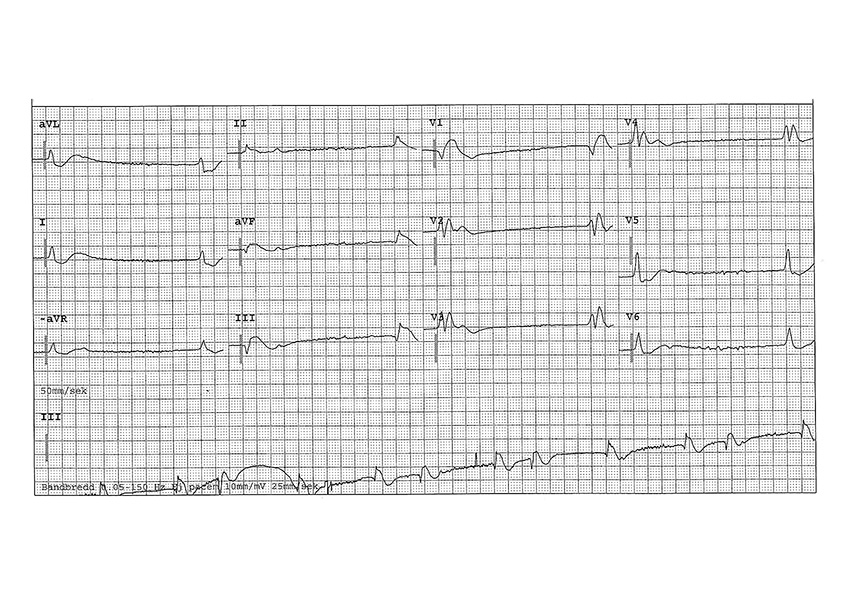

Akut koronarangiografi med beredskap för perkutan koronarintervention är indicerat vid misstänkt kranskärlsocklusion. Faktorer som talar för ischemiutlöst hjärtstopp är ventrikelflimmer/pulslös ventrikeltakykardi som initial rytm, regional hypokinesi på ultraljud och ST-höjningar på EKG efter ROSC [41, 42]. EKG direkt efter ROSC kan dock vara svårvärderad: i en studie bedömdes att 18 procent av patienter med ST-höjningar på EKG inom 8 minuter av ROSC inte behövde perkutan koronarintervention [43]. Därför rekommenderas seriell EKG. Datortomografi genomförs beroende på misstänkt tillstånd (till exempel lungemboli/blödning), men bör undvikas om patienten är instabil och det fördröjer nödvändig intensivvård. Spontan subaraknoidalblödning kan orsaka hjärtstopp, med cirka 20 procents överlevnad [44].

Fall 1. En 66-årig man med diabetes ringde 112 på grund av bröst­smärta. EKG tolkades som ST-höjningsinfarkt och patienten kördes till sjukhuset för direkt angiografi. Vid ankomst till ambulanshallen fick patienten hjärtstopp. Den initiala rytmen var asystoli. Patientnära blodprov visade glukos 66 mmol/l och kalium 7,1 mmol/l. Patienten behandlades med adrenalin 1 mg iv bolus vid två tillfällen, kalciumglubionat 100 mg/ml 20 ml iv bolus, insulin 10 E iv bolus och fick tillbaka spontan cirkulation. Förnyat EKG visade ingen kvarstående ST-höjning. Den tidigare ST-höjningen var troligen ett hyperkalemiutlöst pseudoinfarktmönster [60]. Patienten avled 6 dagar senare till följd av hypoxiska hjärnskador.

Fall 2. En 68-årig man utvecklade pleuritisk bröstsmärta och ringde 112 dagen därefter på grund av svimfärdighet. Vid ankomst till akuten visade EKG ett högergrenblock. Cirka 20 minuter senare förlorade patienten medvetandet och förnyat EKG visade ett uttalat högergrenblock. Patienten utvecklade strax därefter hjärtstopp och behandlades under pågående hjärt–lungräddning med 50 mg alteplas som bolusinjektion mot misstänkt massiv lungembolisering och återfick spontan cirkulation. Datortomografi av torax bekräftade diagnosen och patienten skrevs ut från sjukhuset 5 dagar senare utan neurologiska sekvele.